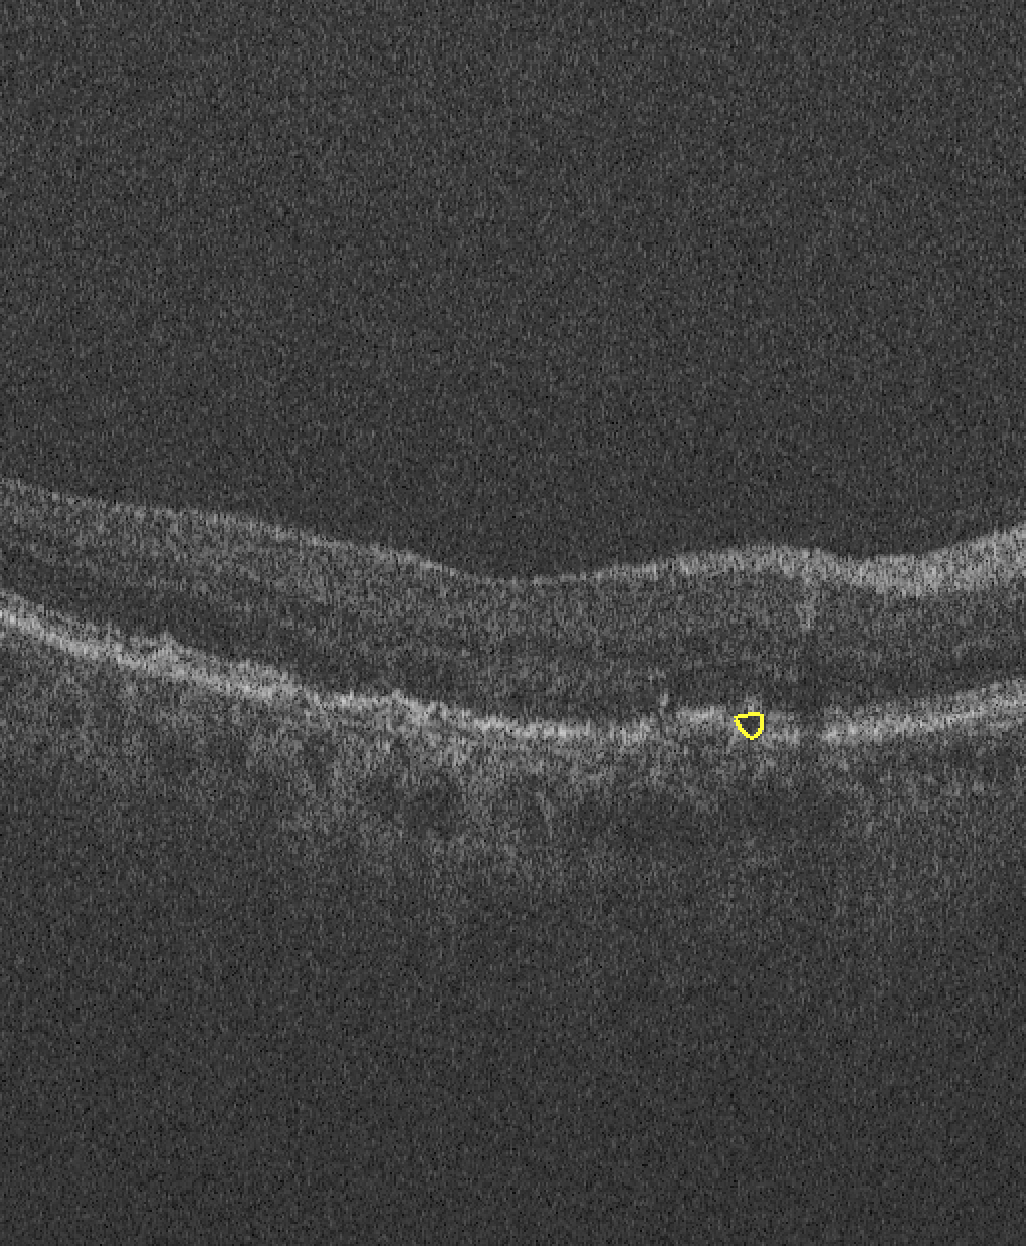

The images used in this study are provided by the MICCAI RETOUCH Group[1]. There were 3 training data sets and a total of 70 volumes, with 24 volumes acquired with each of the two OCT imaging devices: Cirrus (Zeiss) and Spectralis (Heidelberg), and 22 volumes acquired with T-1000 and T-2000 (Topcon, collectively referred to by the manufacturer name in the rest of paper). For each volume from these three devices, the numbers of B-scans were 128, 49 and 128, respectively. Three different types of fluid, namely the intraretinal fluid (IRF), subretinal fluid (SRF) and the pigment epithelial detachment (PED) were manually labeled and provided as ground truth. Although not all B-scans contained fluid, there was at least one type of fluid in each volume. Topcon images with and without macular edema are shown in Fig 1 for each commercial device.

| (a) Cirrus | (b) Spectralis | (c) Topcon |